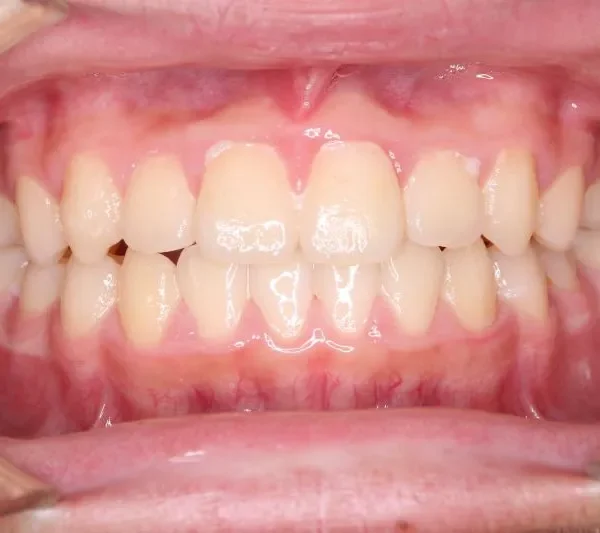

【子供の矯正(一期)】叢生・切端咬合・受け口・永久歯が生える隙間がない・非抜歯症例・8歳男子【K.Y様】

初診時年齢 小学校3年生 (男性) 主訴 前歯の噛み合わせが悪い

診断名 切端咬合 装置名

状態 永久歯が生える隙間がない(叢生)

受け口(下顎前突/反対咬合)

切端咬合

上の歯も下の歯も歯が生えるスペースが少ない為ガタガタしています。

前歯同士が上下で付き合わせる様に噛み(切端咬合)、

その横の歯は上の歯が下の歯の後ろにきて噛んでいる状態です(反対咬合)

初診

治療終了後